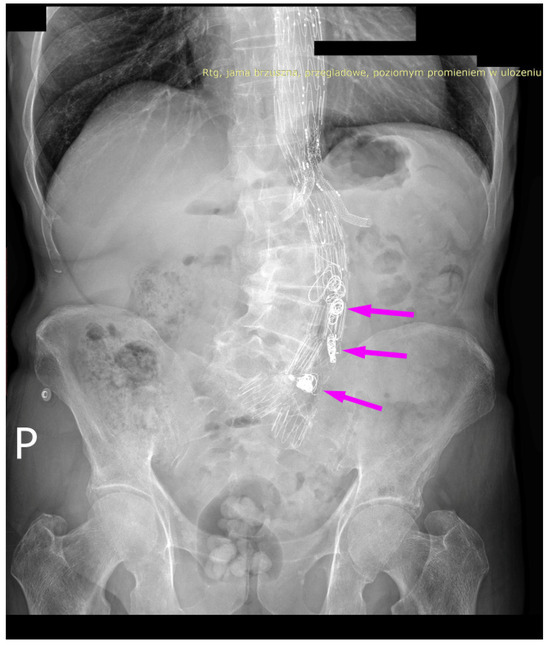

We present the case of an 82-year-old male patient who appeared in the emergency department due to progressive weakness and abdominal pain (2024). Due to a drop in blood pressure to 80/40 mmHg, a continuous infusion of norepinephrine was initiated. The hemoglobin level was approximately 5.1 g/dL. His medical history included generalized atherosclerosis, renal failure, and a thoracoabdominal aortic aneurysm (TAAA) treated with endovascular aneurysm repair (EVAR) using stent-graft implantation 4 years earlier (2020). At that time, the angio-CT scan revealed an aneurysm starting just below the celiac trunk, extending to the superior mesenteric artery (SMA) and both renal arteries (RAs). The maximum diameter of the aortic aneurysm was 51 mm; however, the left common iliac artery measured 41 mm in diameter, an indication for thoracoabdominal stent graft implantation. The aortic aneurysm itself was completely free of mural thrombus. The patient had also experienced a heart attack 16 years earlier and a transient ischemic attack (TIA) 2 years earlier. Following the stent graft implantation, he underwent multiple successful interventions to address endoleaks. One year after implantation, endovascular treatment with embolization coils was performed to eliminate leakage from the lumbar artery (LA) (2021). Three years post-implantation, he was admitted to address leakage from the inferior mesenteric artery (IMA) using embolization coils as well (Figure 1) (2023). In 2024, an X-ray and CT scan revealed a rupture in a branch of the stent graft located in the SMA in its middle part, along with an enlarged aneurysm sac (74 mm) due to the fracture and leakage (Figure 2, Figure 3, Figure 4 and Figure 5). The angio-CT scan did not reveal any contrast extravasation beyond the vessel wall. However, significant contrast leakage was visible in the area of the visceral arteries within the aneurysm sac. The implanted device was the Zenith t-Branch Thoracoabdominal Endovascular Graft, and the ruptured branch was identified as the Bentley BeGraft (Bentley InnoMed GmbH, Hechingen, Germany). Urgent surgical intervention was performed. Intraoperative angiography (IA) showed a breach in the continuity of the BeGraft material within the SMA, with contrast leakage into the aneurysm sac (Figure 6 and Figure 7). To address the leakage and restore the continuity of the SMA branch, an additional BeGraft Plus 8 × 57 mm was implanted into the damaged branch. Subsequent IA and control CT scans confirmed the elimination of leakage, restoration of stent graft continuity, and revascularization of the SMA (Figure 8, Figure 9 and Figure 10). The surgery was completed without complications, and the patient was discharged home in good general condition. The patient returned for follow-up 3 weeks after the last intervention. An angio-CT examination was performed, revealing no enlargement of the aneurysm sac (74 mm), confirming the elimination of the endoleak, and demonstrating successful revascularization of the SMA. Ongoing follow-up will be continued.

Figure 1. Thoracoabdominal branched stent-graft in the lumen of aorta and visceral arteries. Embolization coils are marked with arrows. Abdominal X-ray.